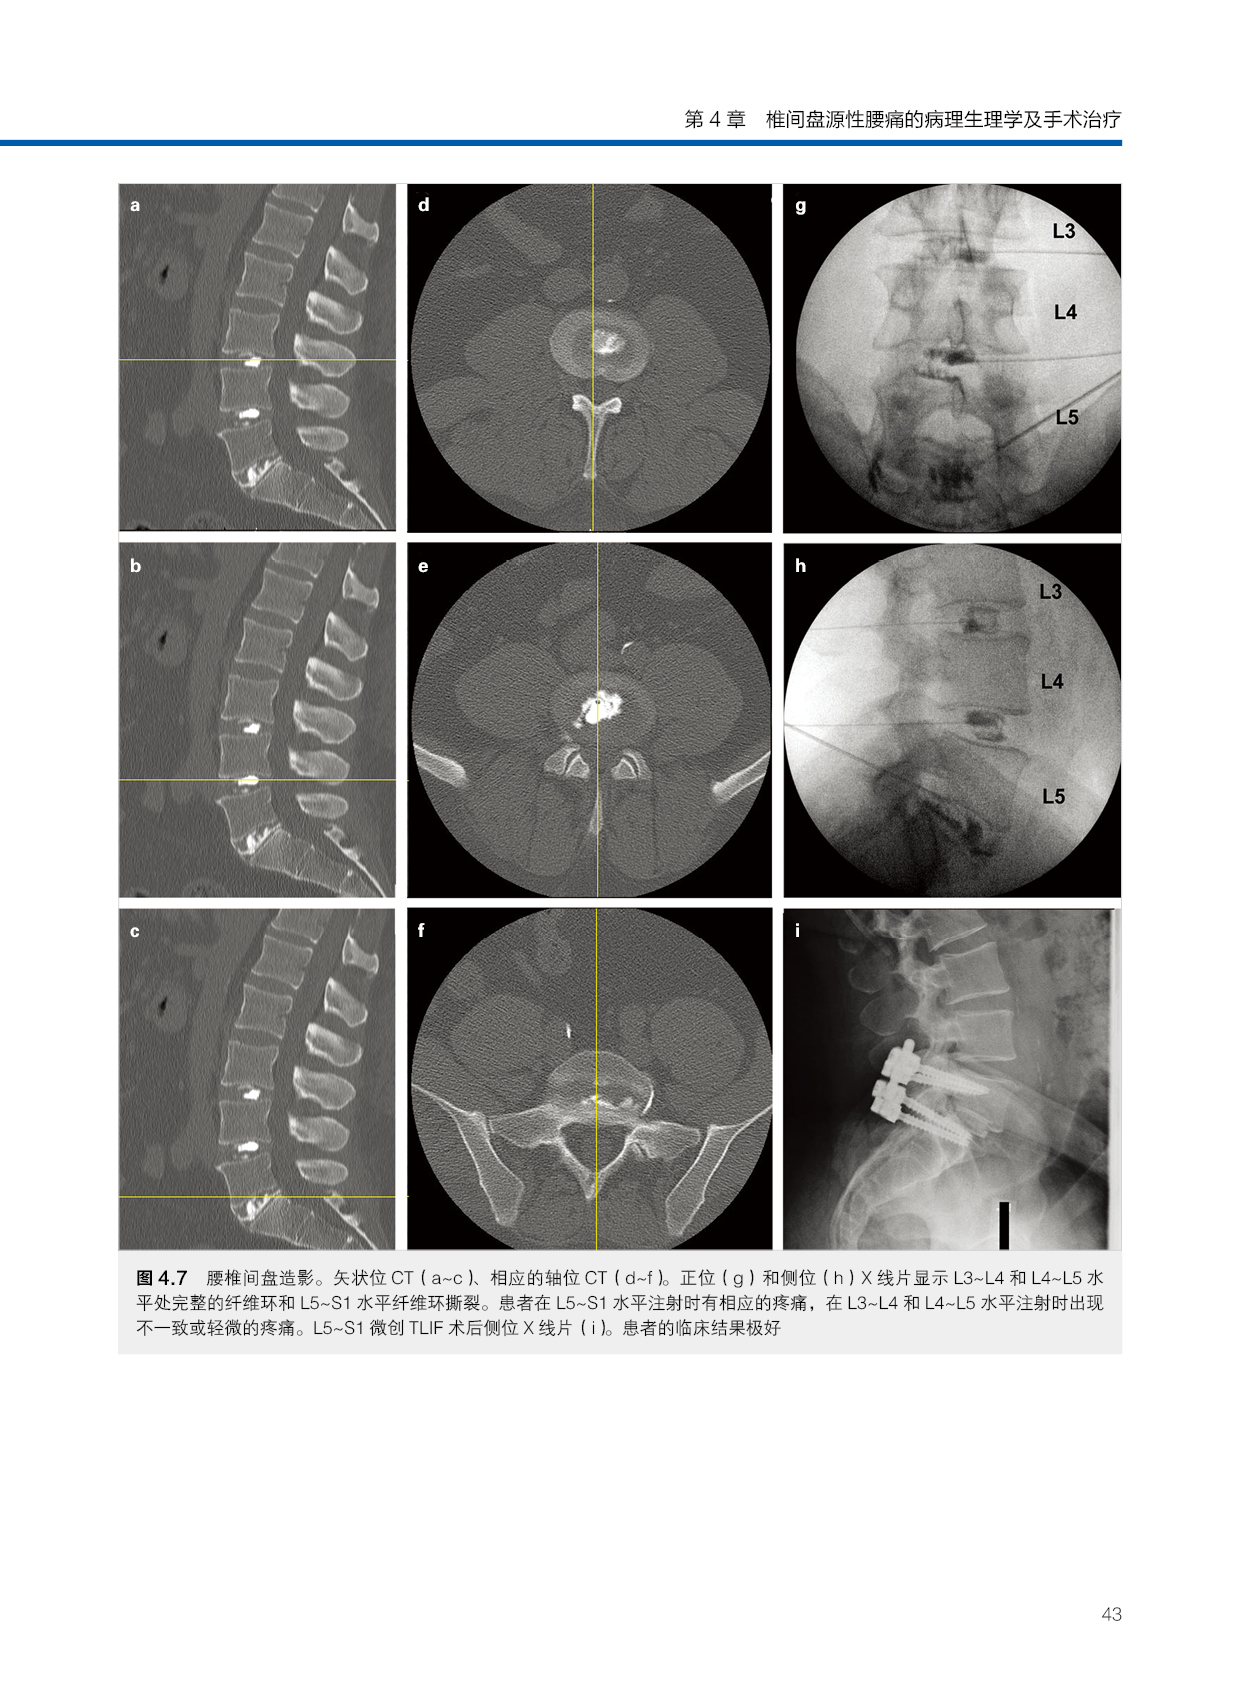

第4章 椎间盘源性腰痛的病理生理学及手术治疗37